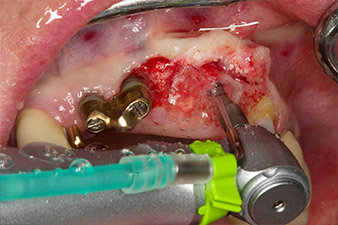

Une fois la cicatrisation primaire obtenue, les tissus mous ont été formés à l'aide du bridge doublé à la base. Deux mois plus tard, la zone a été exposée au moyen d'une incision de la crête alvéolaire légèrement orientée côté palatin (Fig 2). Les dimensions de l'os alvéolaire se sont avérées suffisantes en position 22. Les Figures 2 et 4 illustrent la préparation du lit implantaire, le taraudage et la pose de l'implant à l'aide de l'Implantmed.

Afin de compenser la perte osseuse parodontale et d'obtenir un résultat esthétiquement satisfaisant, la pose de l'implant a été associée à une régénération osseuse guidée (GBR) avec matériau de substitution xénogénique et membrane collagène. (Fig. 5 et 6).